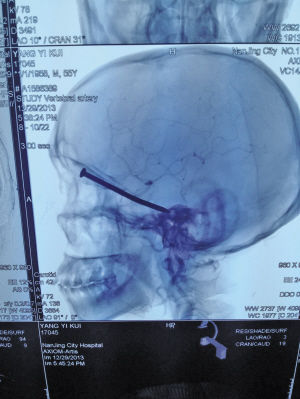

CT显示,铁钉从老杨左眼上方整个扎进大脑。 CT显示,铁钉从老杨左眼上方整个扎进大脑。

当天夜里,疼痛一阵高过一阵,眼睛也肿得老高,老杨一夜未睡。熬到了天亮,老杨开始不住地呕吐,被家人紧急送往第一医院。眼科医生一看,估计里面有东西,便让老杨去拍个CT。拿到片子,医生被吓了一跳:一根七八厘米长的铁钉从左眼上方直扎大脑,整个扎了进去。